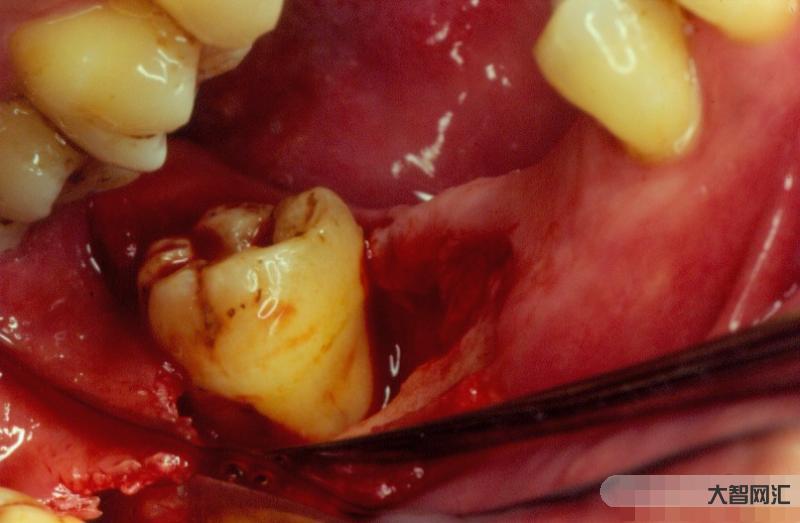

正常健康的牙龈颜色为粉红色,质地坚韧,牙龈边缘紧紧包裹着牙齿。牙周病患者的牙龈颜色为鲜红色或深红色,牙龈边缘的位置也发生了显著变化。牙周病患者在刷牙和咬硬物时经常伴有牙龈出血,严重者早上起床时会有血迹和严重口臭。

牙龈炎是什么?

牙龈炎一般分为轻、中、重:

如果进一步发展到严重程度,可能会进一步发展为牙周炎,导致牙龈萎缩;

进一步发展为相应吸收萎缩的牙槽骨,症状过程不可逆,最终导致牙齿松动脱落。